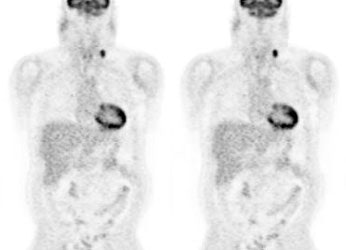

Monitor response to therapy in lymphoma: The patient shown below is a teenage male with Hodgkins disease. The pre-therapy scan confirmed disease only above the diaphragm. The post-therapy scan was performed following two cycles of chemotherapy and demonstrated complete resolution of all sites of disease. Early data indicates that following effective chemotherapy, there is a rapid decrease in metabolic activity within the tumor. Click images to view rotating avi files (note para-cardiac and costophrenic angle nodes can also be seen on these images). |

|